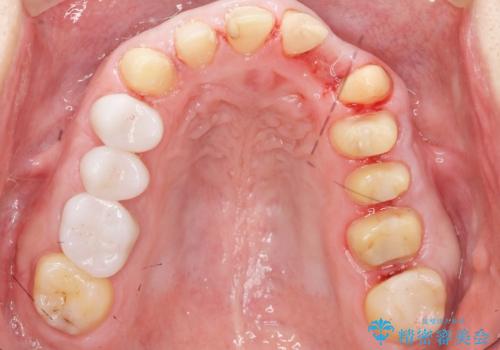

歯頚ラインが変えられないことや天然歯を削るリスクをご理解頂いた上で、オールセラミッククラウンによる補綴治療を行いました。(見えない奥歯のみ天然歯のままとしました)

それ以外の歯は神経をとらずに済むよう、慎重かつ丁寧に歯の形態を整えました。

クラウンの色味・形態の修正や患者様のお仕事のご都合で来院できない期間があったことにより、予想より治療期間が長くなってしまいましたが、審美的な仕上がりにご満足頂けました。

クラウンの色味に関して、自然な白さ(シェードA1~NW0.5)のクラウンを作製・試適したところ「もっと白くしたい」と希望され、当院で最も明度の高い色(シェードNW0)に修正しました。

被せ物の種類:オールセラミッククラウン スタンダード (シェード:NW0)